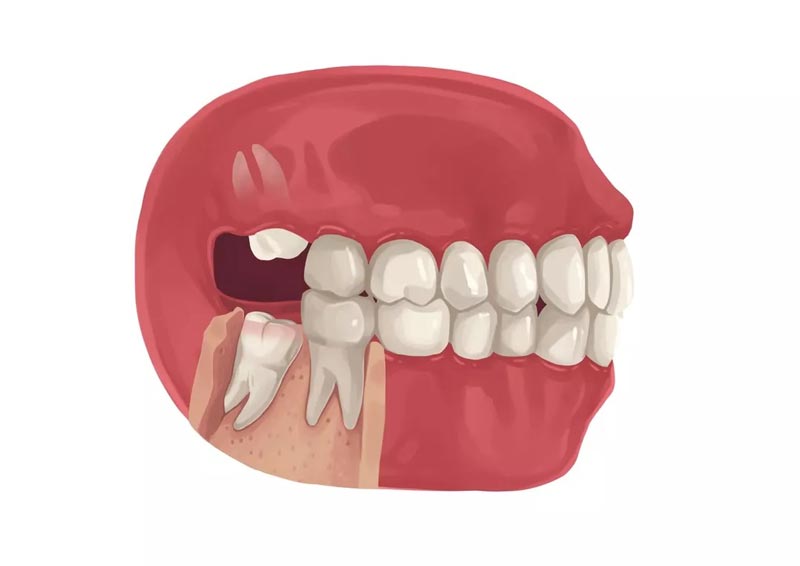

دندان های عقل یا (wisdom teeth) آخرین دندان های دائمی هستند که از لثه بیرون می آیند. دندان های عقل ۴ عدد هستند و در هر فک ۲ عدد از این دندان ها در انتهای قوس فکی وجود دارد. دندان عقل معمولاً در سنین ۱۷ تا ۲۵ سالگی ظاهر می شود و در برخی افراد موجب درد جزئی تا شدیدی می شود. اگر شما هم جز این افراد هستید و درد دندان عقل را تجربه میکنید، حتماً این مقاله را بخوانید تا درباره علل و بهترین روشهای درمان و تسکین دندان عقل، اطلاعات کاملی به دست بیاورید. قبل از ادامه پیشنهاد می کنیم برای انجام هر گونه خدمات دندانپزشکی به دندانپزشک خوب در تهران مراجعه کنید.

دلایل درد دندان عقل ممکن است متنوع باشد، اما دو عامل اصلی آنها شامل ایجاد فشار بر روی دندان و عفونت میباشد. اکثر موارد درد دندان عقل ناشی از فشار بر روی دندان هستند. زمانی که دندان عقل شکل میگیرد، در بیشتر موارد فضای کافی برای آن در دهان وجود ندارد، بنابراین ظاهرا فشاری بر دندانهای اطراف وارد میشود. این فشار ممکن است باعث درد و سردرد شود. در برخی موارد، دندان عقل به خوبی در دهان قرار نمیگیرد و به جای آن در فضای موجود در دهان، برخی باکتریها ایجاد میشود. باکتریهای موجود میتوانند باعث عفونت شوند و به علت درد و سردرد شوند.

خیر، دندان عقل همیشه درنمیآید. در بسیاری از افراد، یک یا چند دندان عقل ممکن است بهطور کامل نهفته باقی بمانند و هرگز از لثه خارج نشوند. دلایل این اتفاق میتواند شامل کمبود فضای کافی در فک، موقعیت نادرست دندان یا موانع ساختاری در مسیر رویش آن باشد. در برخی افراد نیز تنها بخشی از دندان عقل رشد میکند و باقی آن زیر لثه باقی میماند که میتواند باعث مشکلاتی مانند التهاب و عفونت شود. بنابراین، رشد یا عدم رشد دندان عقل به ساختار فک، ژنتیک و عوامل دیگر بستگی دارد و برای بررسی دقیق آن، عکس برداری رادیولوژی لازم است.

دندان عقل نهفته زمانی رخ میدهد که فضای کافی برای رویش آن در دهان وجود نداشته باشد و در نتیجه، به طور کامل یا جزئی زیر لثه باقی بماند. این وضعیت میتواند بدون علامت باشد، اما در بسیاری از موارد، علائم هشداردهنده ای ظاهر میشود که نشان میدهد باید به دندانپزشک مراجعه کرد. علائم هشدار دهنده دندان عقل نهفته: